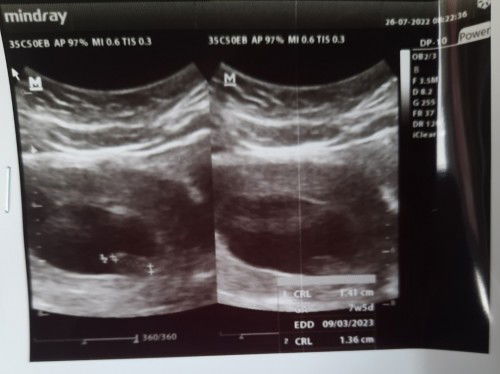

Pendarahan usia 7w6d opname dan harus kuret

Melanjutkan sharing saya kemarin setelah muncul flek lalu usg divonis kandungan lemah dan diberi penguat justru pendarahsn hebat. Kenudian dibawa ke igd dan disarankan kuret. Bunda ada yg mengalami hal sama?

7w2d janin tidak berdetak divonia kandungan lemah.